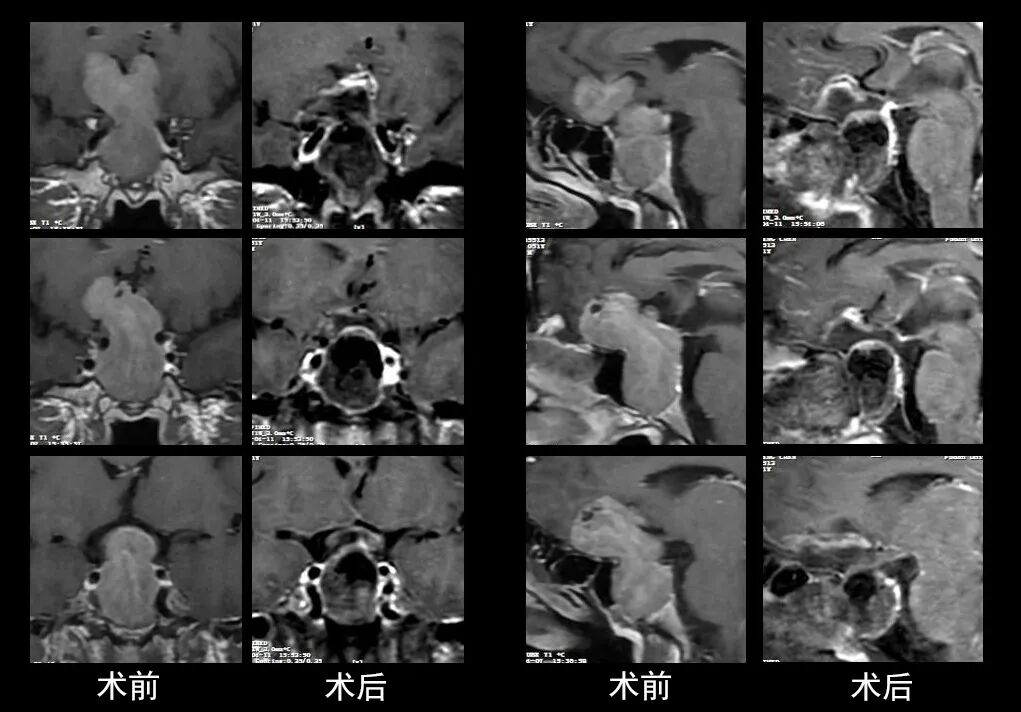

本研究中采用联合手术策略的代表性病例展示:

左右滑动查看更多

图片

case 7

case 8